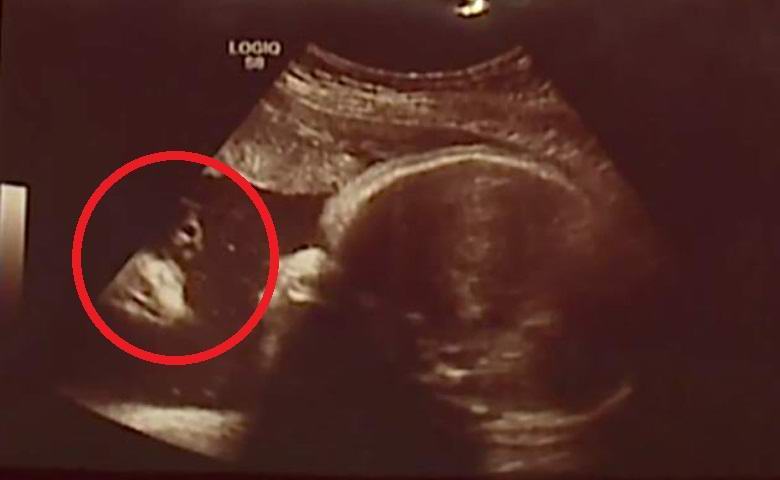

Manželé z amerického města Chambersberg ve státě Pennsylvania nemohla uvěřit svým očím, když na obrázku během ultrazvukového vyšetření plodu v děloze objevila se jejich matka, nyní narozená dcera Briella jednoznačné náboženské znamení. Na levé straně fotografie objevila se postava dlouhovlasého vousatého muže ve světlém rouchu při pohledu přímo na tvář plodu. Jak asi uhodnete, budoucnost rodiče okamžitě cítili, že to byl obraz Ježíše Krista.

Než pár viděl tento ultrazvuk, oni velmi se báli, že na jejich druhou dceru čeká podobný osud, jedinečný obraz však přiměl milence tomu věřit že s dívkou bude vše v perfektním pořádku. Američané hodně modlil se a dokonce začal chodit do kostela. A jejich modlitby byly zodpovězeny Bohem. Briella se narodila zcela zdravá. Prezentováno zde Fotografie páru byla zarámovaná a zavěšená na zdi.